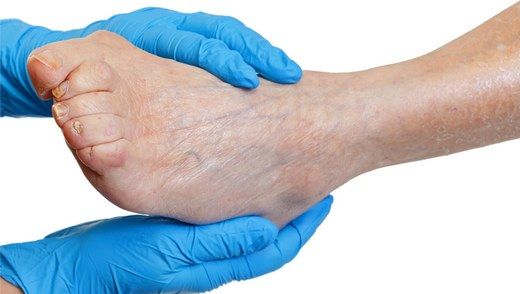

Kas Sinir Hastalıkları: Belirtileri ve Tedavisi Kas sinir hastalıkları, kasların ve sinir sisteminin etkileşimi sonucu ortaya çıkan, genellikle hareket kabiliyetini etkileyen bir dizi durumu kapsamaktadır. Bu hastalıklar, kas zayıflığı, kas atrofisi ve motor sinirlerin hasar görmesi gibi belirtilerle karakterizedir. Bu makalede, kas sinir hastalıklarının belirtileri, nedenleri ve tedavi yöntemleri hakkında ayrıntılı bilgi verilecektir. Kas Sinir Hastalıklarının Belirtileri Kas sinir hastalıkları, bireylerde çeşitli belirtilerle kendini gösterebilir. Bu belirtiler, hastalığın türüne ve ciddiyetine bağlı olarak değişiklik gösterebilir. Genel olarak karşılaşılabilecek belirtiler şunlardır:

Kas Sinir Hastalıklarının Tanısı Kas sinir hastalıklarının tanısı, klinik muayene ve çeşitli testler ile konulur. Tanı sürecinde kullanılan yöntemler şunlardır: